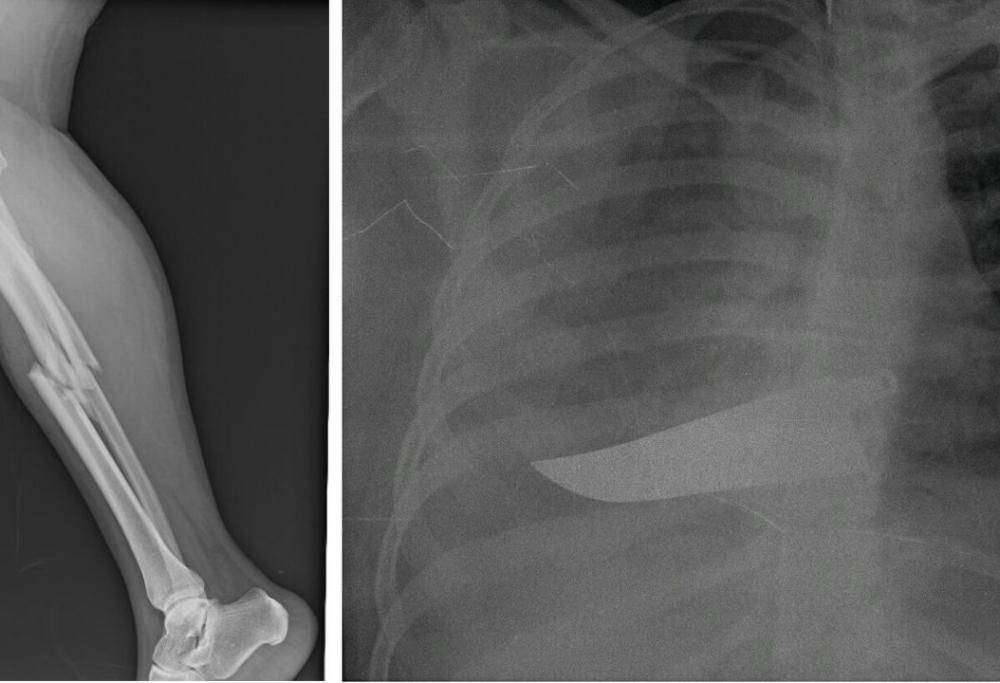

Si intitola significativamente “L’invisibilità non è un superpotere” e racconta il dramma delle donne che arrivano al Pronto Soccorso a seguito di violenze.

La mostra, che parla di questa tragedia silenziosa in modo inedito attraverso le radiografie (anonime) delle vittime di violenza, è stata allestita nell’atrio dell’Ospedale San Carlo di Milano dove resterà visibile fino all′8 dicembre 2019. Organizzata dall’ASST Santi Paolo e Carlo di Milano e dalla Fondazione Pangea Onlus si pone l’obiettivo di portare a galla un problema purtroppo ancora sommerso.

Credits photo, mostra: “L’invisibilità non è un superpotere